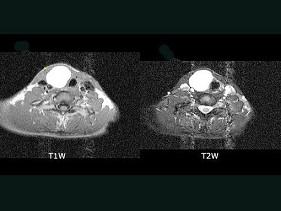

问题 女性,46岁,右颈部无痛性包块,质软,MRI检查如图所示,请选择最可能的诊断 ( )

选项 A、甲状腺腺瘤 B、甲状腺炎 C、甲状腺胶体囊肿 D、甲状腺单纯囊肿 E、甲状腺癌

答案 C